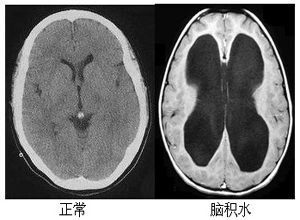

胎兒腦積水,又稱之為先天性腦積水,在影像學(xué)上面主要表現(xiàn)為外部性腦積水,或者是交通性腦積水。外部性腦積水,表現(xiàn)為雙側(cè)廣泛硬膜下積液,這種情況下,大部分和胎兒在母親體內(nèi)存在宮內(nèi)窘迫和宮內(nèi)缺氧,出生以后與新生兒窒息和新生兒缺氧缺血腦病出血有關(guān)。交通性腦積水,通常和患兒出生以后,新生兒顱內(nèi)出血,新生兒蛛網(wǎng)膜下腔出血,新生兒顱內(nèi)感染有關(guān),這些疾病通常會(huì)導(dǎo)致上矢狀竇蛛網(wǎng)膜顆粒吸收腦脊液障礙。